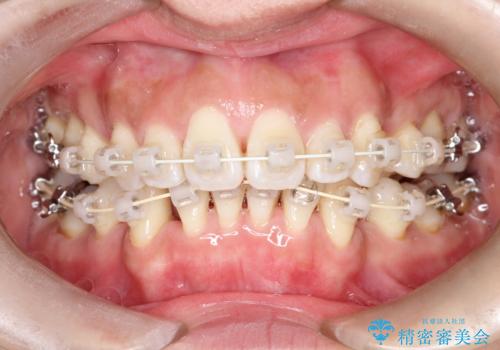

- 矯正装置

- 審美装置

- 治療期間

- 2年1ヶ月

- 出っ歯がきになるとのことで来院されました。

上顎の前歯は前方に傾斜しており、下あごの前歯にもガタガタがありました。

上下左右の小臼歯を合計4本抜歯して矯正することとしました。